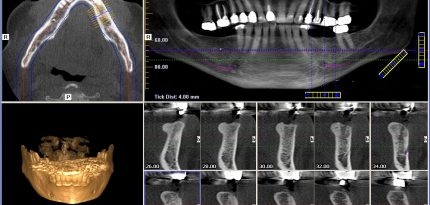

3D Cone Beam Computed Tomography (CBCT)

A 3D CBCT produces three dimensional (3-D) images of your teeth, maxillary sinuses, large nerves and bone in a single scan. Looking at these structures in 3-D can provide more spatial information beyond what a flat 2D x-ray would show, allowing us to plan in greater detail for more invasive and complex procedures. 3D CBCT scans are typically taken for wisdom teeth, dental implant and root canal related procedures.